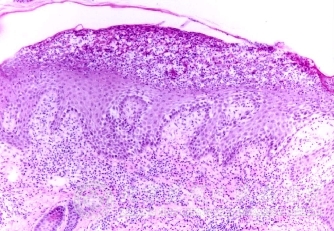

北京京城皮肤医院指出,早期梅毒的发病机理:早期梅毒13天达高峰,随之巨噬*出现,病灶中浸润的淋巴*以t*为主。梅毒螺旋体见于硬下疳中的上皮*间隙中。